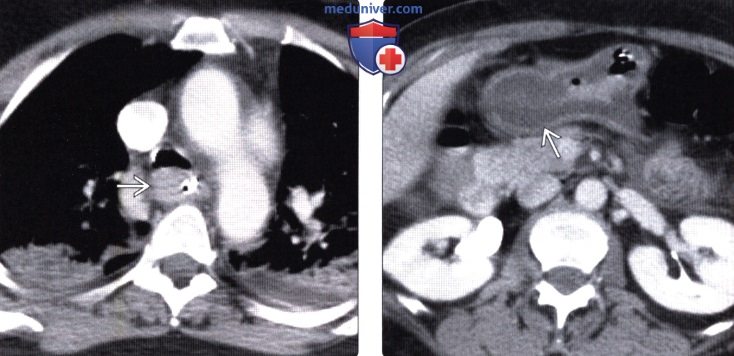

• КТ:

о Острая фаза:

— Симптом «мишени»: чередование гиперденсной слизистой оболочки пищевода, накапливающей контраст, и гиподенсной подслизистой основы

— Перфорация пищевода: пневмомедиастинум, жидкость в плевральной полости

(Слева) На аксиальной КТ, выполненной пациенту через два часа после приема внутрь химического агента, определяется выраженное утолщение стенки пищевода, а также двухсторонний аспирационный пневмонит.

(Справа) На аксиальной КТ с контрастным усилением у этого же пациента определяется значительное утолщение стенки желудка и отек подслизистой основы, что является проявлением коррозивного гастрита.